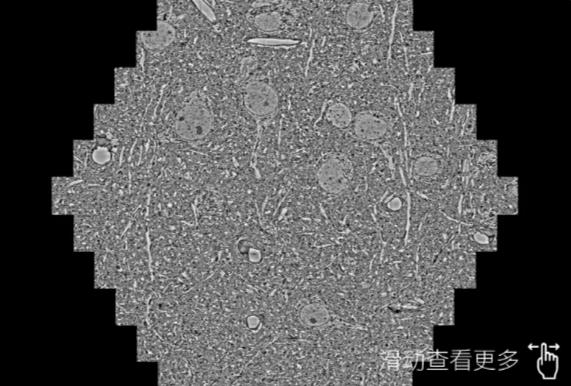

鼠脑切片。左图使用塔城蔡司塔城扫描电镜MultiSEM706对165μmx143pm面积区域成像,耗时仅需1.5秒。右图为鼠脑切片中30μm区域放大效果。样品由芝加哥大学B.Kasthuri提供。